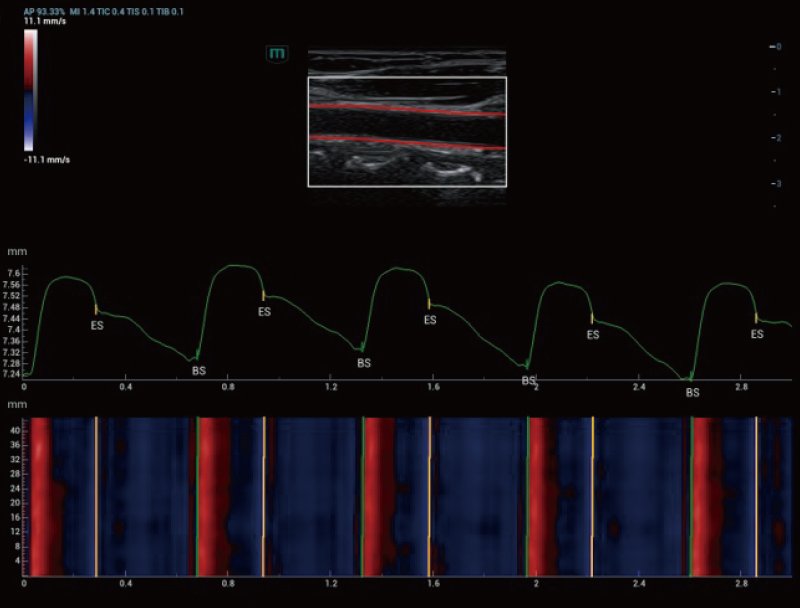

Resona A20 introduce una nuova generazione di strumenti per l'analisi quantitativa vascolare, con l'analisi della velocit├Ā dell'onda di polso vascolare e dello stress di parete basata sui dati RF. Questi progressi aiutano a valutare la sclerosi vascolare arteriosa.

Holo-PWV

Arteria carotide | Holo-PWV